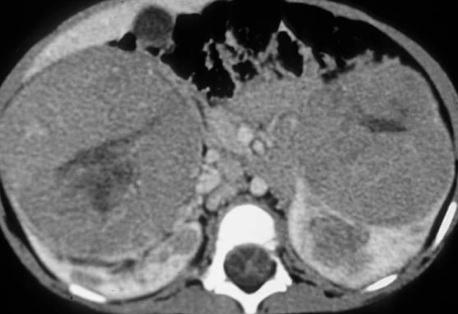

The next best step in management of this patient with a metastatic renal tumor is